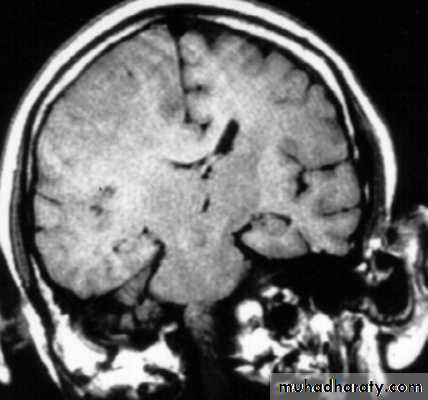

3. Brainstem and hemispheric (Cerebral) Contusion

These are areas of bruising and swellings with intact pia arachnoid, localized or generalized oedema and haemorrhage due to tearing of blood vessels.

3. Cerebral Contusion

Clinical presentations:

1. Prolonged periods of unconsciousness.

2. Focal neurological deficits that persist for longer than 24 hours.

CT scans demonstrates contusions as small areas of haemorrhage in the cerebral parenchyma.

Contusions may resolve with the accompanying deficits or they may persist.